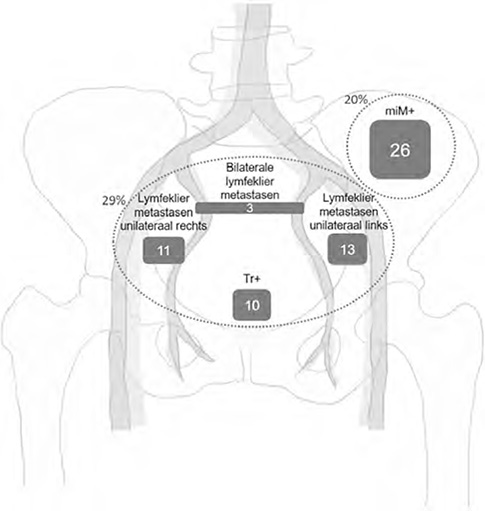

De mediane tijd tot BCR was 9 maanden (interkwartielafstand (IKA) 3–18). Persisterend PSA (PSA ≥ 0,1 ng/ml bij eerste follow-up) werd vastgesteld bij 66/130 patienten (51%). Bij herstadiering met PSMA-PET/CT was de mediane PSA 0,33 ng/ml (IKA 0,24–0,65). PSMA-zichtbare ziekte werd gedetecteerd bij 63/130 patienten (48%), van wie 37/63 (59%) beperkt tot het bekken – 16/37 (43%) met lymfeklieren aan de ipsilaterale zijde van de verwijderde positieve lymfeklier. Bovendien werd bij 26/63 (41%) patienten ziekte buiten het bekken (miM +) gevonden (figuur 13.1). Univariate Cox-regressieanalyse toonde aan dat persisterend PSA het risico op een door PSMA-PET/CT gedetecteerd recidief verhoogde, en een hogere ISUP-score bij RP werd geassocieerd met miM + -ziekte.

Figuur 13.1.

De ziekteverspreiding van PSMA-zichtbare ziekte gedetecteerd door PSMA-PET/CT bij pN1-prostaatkankerpatienten met een BCR. Zevenendertig/130 (29%) patienten hadden ziekte beperkt tot het bekken en 26/130 (20%) had afstandsmetastasen. De cijfers binnen de Vierkanten geven het aantal patienten aan. Tr + = lokaal recidief, miM + = afstandsmetastasen, PSMA-PET/CT = prostaatspecifiek membraan antigeen positronemissie tomografie/computertomografie, BCR = biochemisch recidief

PSMA-PET/CT identificeerde PSMA-zichtbare ziekte bij bijna de helft van de pN1-prostaatkankerpatiënten ten tij – de van een vroeg BCR, waarbij ongeveer de helft van de metastasen beperkt was tot het bekken en een kwart zich buiten het bekken bevond.